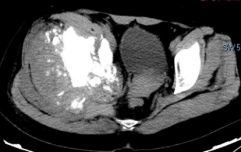

术前影像

日前,安医大一附院骨病骨肿瘤外科胡勇教授团队成功完成一例复杂骨盆Ⅰ+Ⅱ+Ⅲ+Ⅳ区肿瘤切除与3D打印组配式半骨盆假体重建手术。患者为女性,53岁,下腰痛半年余,右侧臀部膨隆,右侧下肢轻度浮肿。右侧髂棘髂窝及臀部可触及巨大肿物,压痛明显,右髋外展前屈活动受限,右侧大腿感觉麻木,右足感觉运动正常。骨盆肿瘤切除重建是骨科专业中难度极大、风险极高的手术。骨盆肿瘤约占原发骨肿瘤的3%~4%,其中以软骨系统肿瘤最为多见,其次为骨巨细胞瘤、成骨肉瘤等,儿童尤文肉瘤亦好发于骨盆。

骨盆恶性肿瘤常潜在发展,由于骨盆位置较深,肿瘤早期很难发现,从第一次出现症状到诊断明确有时需要很长时间,当出现临床症状时,肿瘤体积已较大,因而手术切除相当困难。骨盆肿瘤血供丰富,手术出血多、难度大。另外,骨盆形态特殊,解剖复杂,切除肿瘤的同时,需要重建骨盆结构和肢体功能,技术要求高。